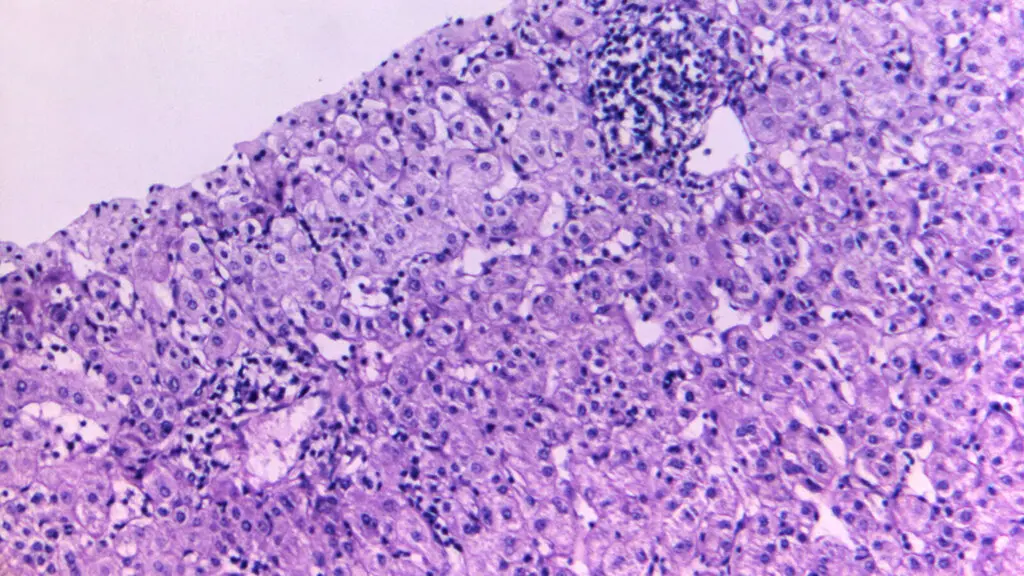

هپاتیت یا التهاب کبد ناشی از عوامل ویروسی میتواند بر توانایی کبد در سوختوساز مواد مغذی و تصفیه خون اثر بگذارد.